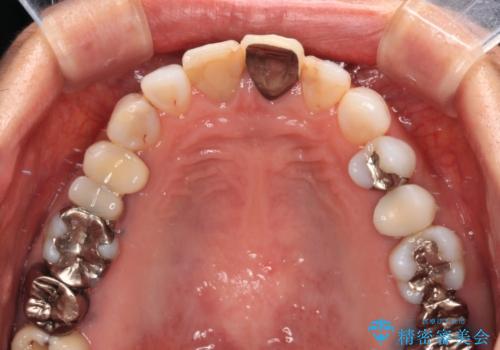

- 変色した保険の前歯のクラウンを交換したいとのことで来院された患者様です。

中心左側の歯はクラウンが装着されており、右側は神経組織が除去されて多少変色している状態でした。

右側の歯も将来的にもっと変色する可能性があるため、前歯2本をオールセラミッククラウンにて補綴治療を行うこととしました。